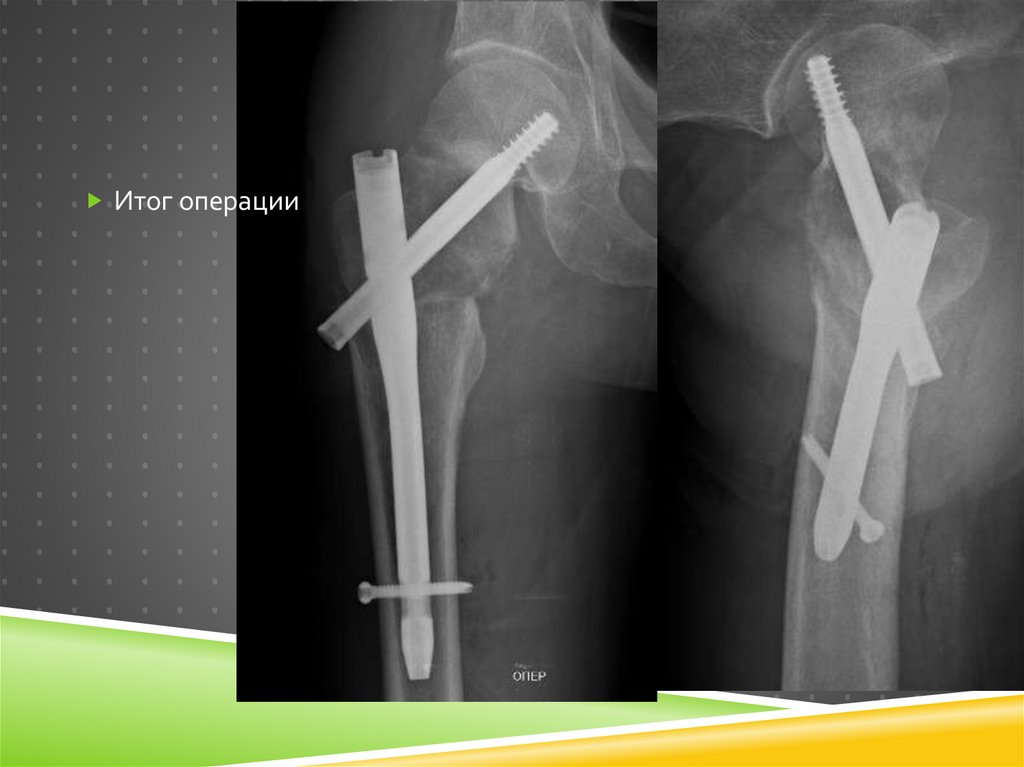

Итог операции

Итог

98.